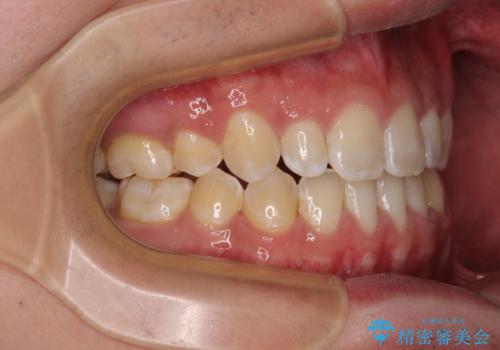

- 受け口傾向の咬み合わせと口元の突出感を気にして来院された患者様です。

受け口傾向特有の狭い上顎歯列であったため、歯列の拡大を補助装置で行い、下顎歯列全体を後方に移動させることとしました。

奥歯の咬み合わせを改善させた後、上下左右の小臼歯(下顎は残存乳歯)を計4本抜歯し、ワイヤー装置にて口元の突出感を改善しながら咬み合わせを整えることとしました。